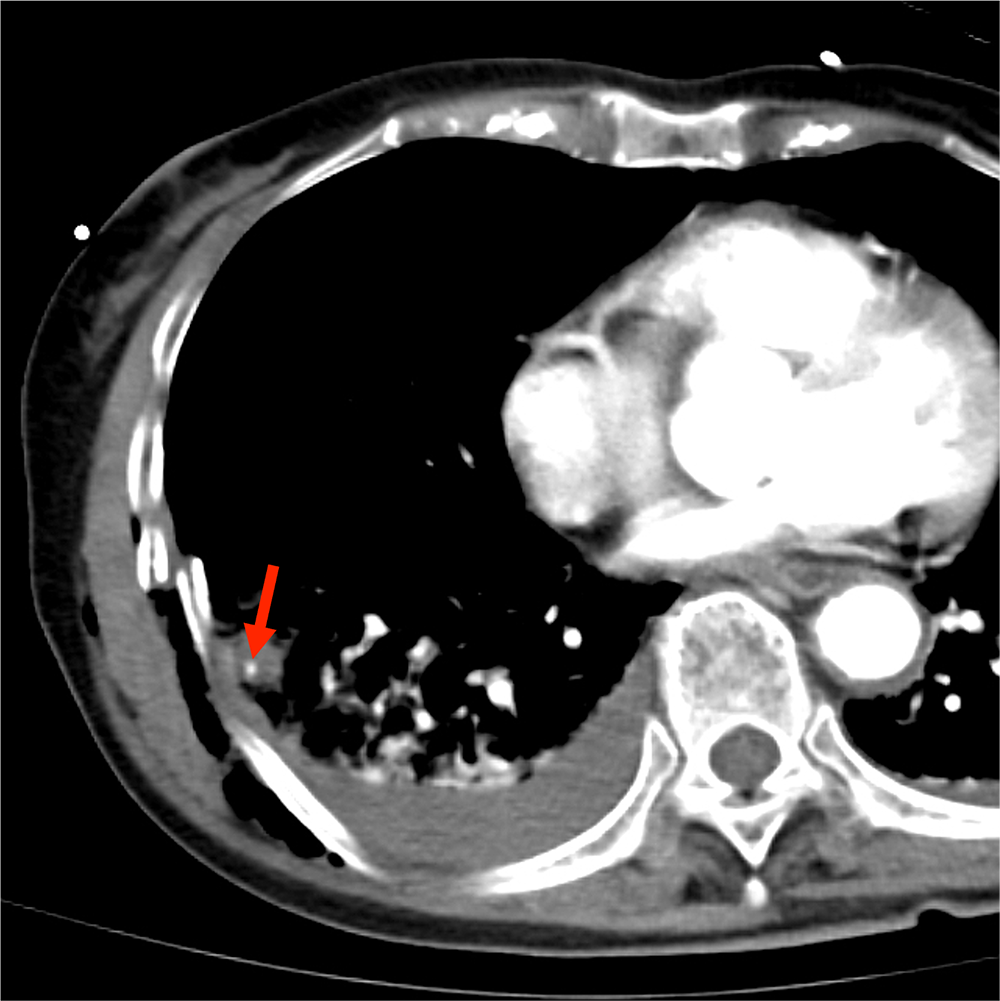

CTでは多発肋骨骨折、外傷性血気胸、肺挫傷、胸壁内気腫が認められた。

挫傷した肺内には結節状構造がみられ、肺気瘤の形成が示唆される。造影CTではこの内部に点状の濃染影が認められ、肺実質内血管外漏出(extravasation in the lung:EVIL)が疑われた。

肺挫傷や血気胸は単純CTでも確認できるが、造影CTを追加することで肺内血管外漏出(EVIL)の有無を確認することができる。

血管外漏出は活動性出血の存在を示唆する兆候で、外傷時のCTではまず確認すべき重要な所見である。腹部や骨盤部での血管外漏出は直ちに手術やIVRの適応になることが多いので、読影の際に見落としてはならない所見として認知されているが、肺挫傷で血管外漏出の有無を確認することの重要性はあまり知られていない。